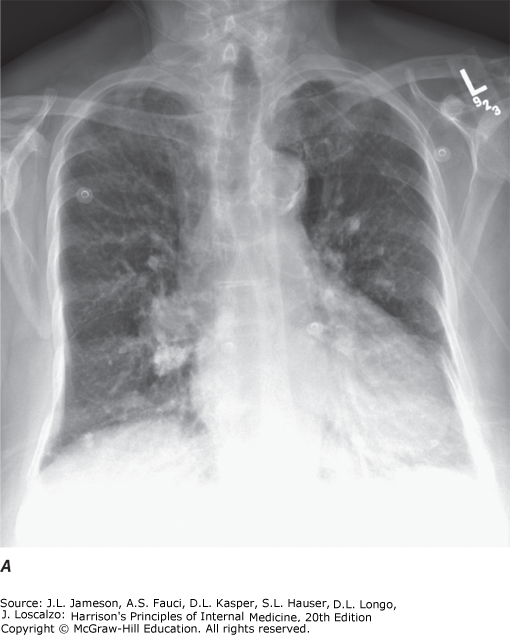

| 11 | Be familiar with diagnostic procedures in respiratory disease | Diagnostic modalities include imaging (chest X-ray, CT/helical CT, MRI, ultrasound, nuclear medicine/V-Q scan, PET scan, virtual bronchoscopy) and tissue-sampling techniques. CT is superior to plain film for mediastinal disease, emphysema characterization, and lung cancer staging. MRI excels at vascular assessment without contrast. |

Imaging Modalities

| Modality | Key Features | Best For |

| Chest X-ray (PA/Lateral) | Integral for parenchyma, pleura, mediastinum evaluation. Decubitus views identify free-flowing fluid. Apical lordotic views visualize lung apices better than standard PA | Initial evaluation of pulmonary disease, pleural disease |

| CT | Cross-sectional images distinguish superimposed densities. Far better tissue density characterization and accurate lesion sizing than plain film. With IV contrast: distinguishes vascular from nonvascular structures | Hilar/mediastinal disease, lung cancer staging, pulmonary embolism, pulmonary nodule characterization |